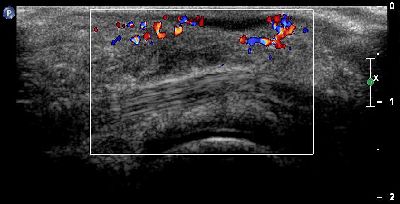

Flogosi plantare (img. 03) flogosi plantare 03